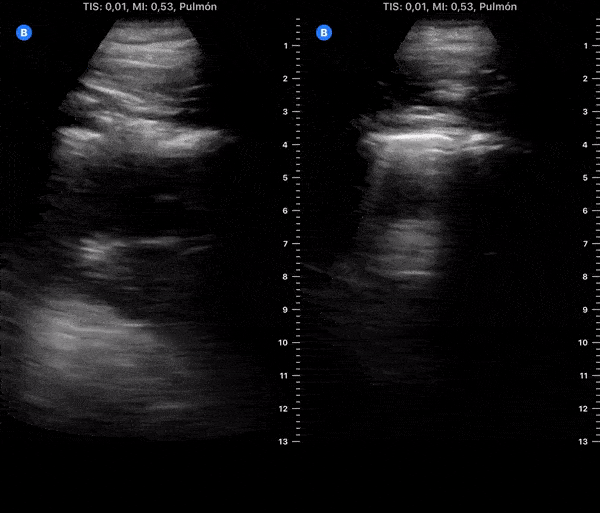

COVID 19 Lung US Disease Progression - Day 17

Day 17 after #COVID diagnosis. Less cough, nausea & more appetite, energy. No fever or dyspnea. SpO2 97%. #POCUS update: right side resolved, left lateral & lower less thickened pleura & B-lines. @yaletung